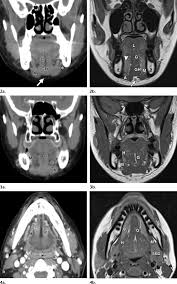

I did some plain research on teeth about the structure and some unusual silhouette deture.